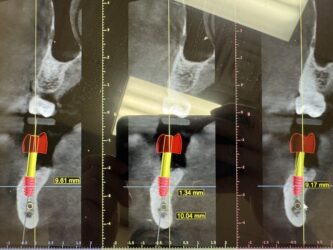

Dr. started the discussion #19 in the forum Implant Tx Planning 2 years ago

These are images of a recent scan.

This is 5 months after #19 implant was explanted (failed 2 weeks after placement) and simultaneous grafting was done.

I have currently planned for a Hiossen 4.5x7mm with buccal veneer grafting. This will be placed relatively deep due to ridge atrophy. What are your thoughts on this deep placement…